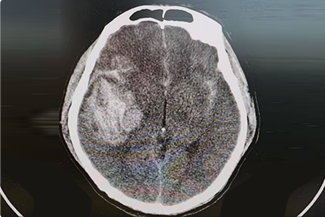

从事神经外科工作30年,擅长脑与脊髓血管类疾病、肿瘤、外伤等疾病的诊断与治疗,尤其擅长神经介入治疗各类脑血管疾病。累计完成介入栓塞颅内动脉瘤2000多例,颅内血管畸形数百例,夹闭颅内动脉瘤数百例,手术颅内与脊髓肿瘤数百例。在脑和脊髓血管病、肿瘤、外伤等方面有丰富的经验和较深造诣。

精通颅内动脉瘤介入栓塞和手术夹闭双技术,系统掌握脑动静脉畸形、颈内动脉海绵窦漏、硬脑膜动静脉漏等颅内血管疾病的诊疗和手术,精通颈动脉、椎动脉狭窄的血管内重建技术,以及颈动脉狭窄的内膜剥脱手术技术。在颅内肿瘤、椎管内肿瘤、颅脑损伤、高血压脑出血等疾病的诊治和手术,脑功能性疾病立体定向手术治疗等方面也积累了丰富的经验。